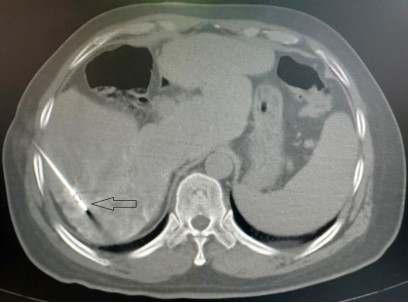

图1 红色圆圈内为肝癌病灶

图2 微波天线穿刺入肝癌病灶内(黑色箭头)